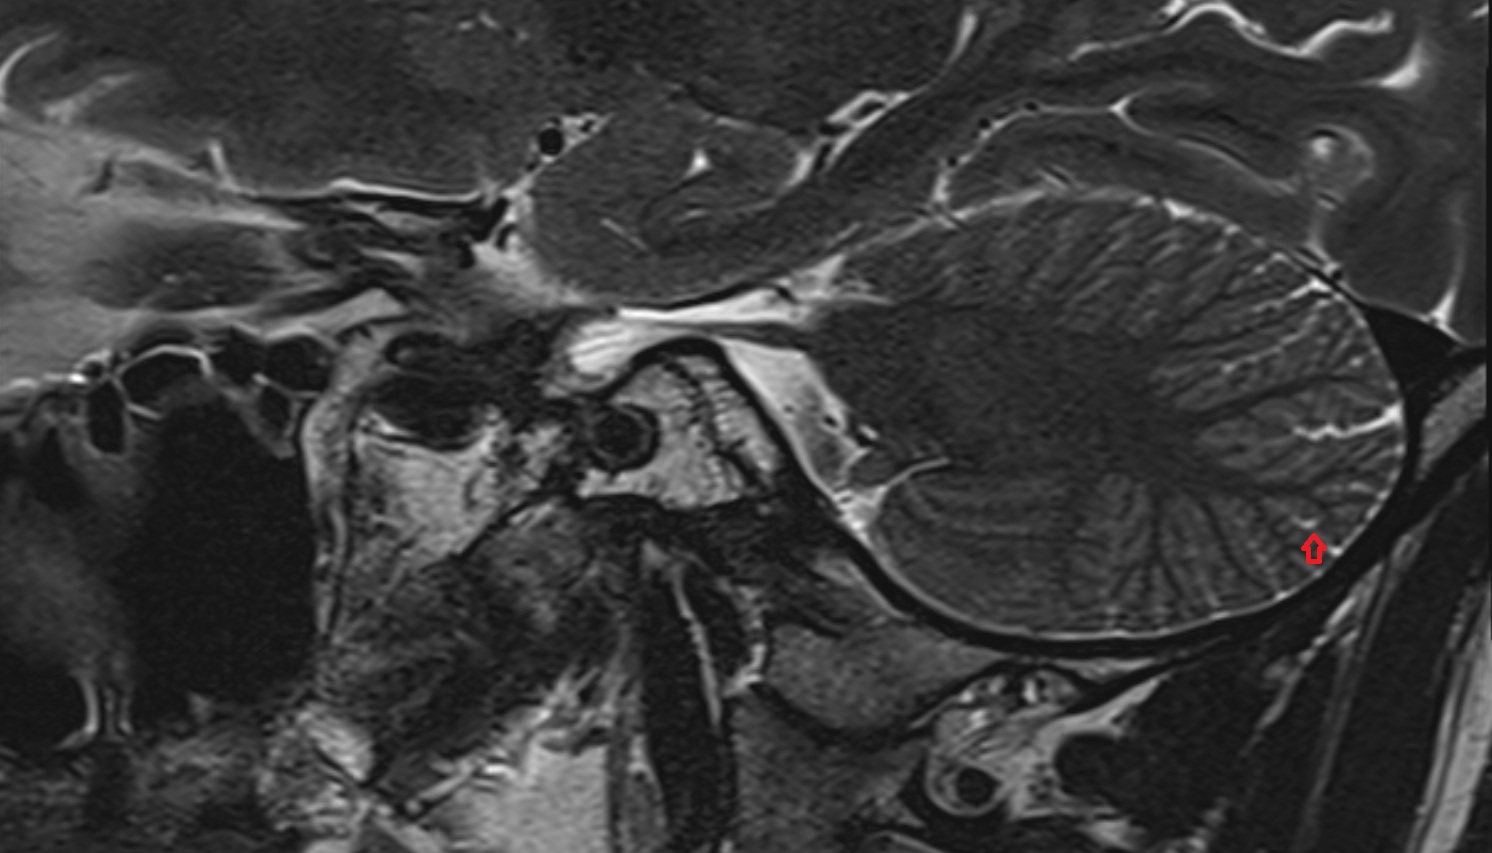

- Cerebellum

- Cerebellar tonsil (H IX)

- Tonsil of cerebellum